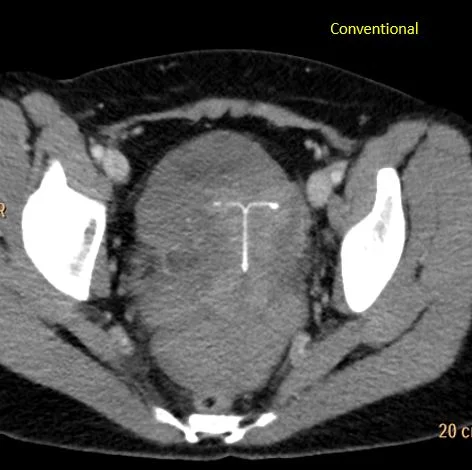

30 year old female with acute onset pain that radiates to her shoulders. Abdomen tender on exam, UPT negative. CT scan obtained, shows large hemoperitoneum with dense clot in the pelvis. Hard to separate clot from the uterus.

On Spectral analysis, easy to separate clot from the uterus. There is also a 1.9 x 1.2 cm right adnexal cyst. Ultrasound shows cyst is likely an involuting corpus luteum.